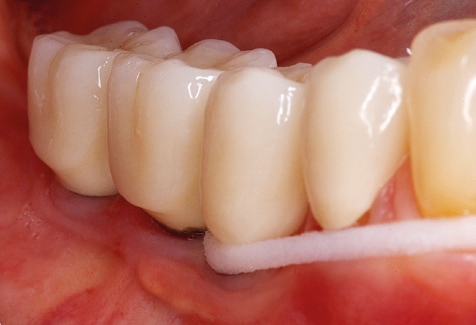

Following machine cleaning of the tooth and implant surfaces, the surfaces of the natural teeth are cleaned manually using standard hand instruments. When performing manual cleaning, particular attention must be given to maintaining the correct angle of application, appropriate sharpness, good support and working with the curette from apical to coronal. Either titanium or carbon curettes should be used for post-cleaning of the implant structures (Fig. 8). In addition to the use of ultrasonic devices, power jet devices can also be used in conservative dentistry. However, it must be taken into consideration that these procedures are not suitable for removing hard deposits and thus they cannot replace the use of hand instruments and ultrasonic instruments completely. In all cases, cleaning is followed by mechanical polishing of the accessible tooth and implant surfaces with polishing cups and polishing compounds (Fig. 9).

Fig. 9: The accessible implant and tooth surfaces are polished with polishing cups and suitable polishing compounds. – Fig. 10: Repeat instruction in the use of appropriate aids for oral hygiene at home should also form part of SPT. – Fig. 11a and b: Clinical situation 12 years after insertion of the prosthetic restoration. During this period, only a veneering ceramic fracture on tooth 47 and the requirement for endodontic treatment of tooth 12 were observed. All restorations are still functioning as intended.

Standardised and regular risk-adapted care in the scope of SPT is the key to treatment success for the clinical long-term success in periodontically compromised patients. This is particularly true for patients fitted with implants following successfully completed periodontal treatment (Fig. 11a and b).